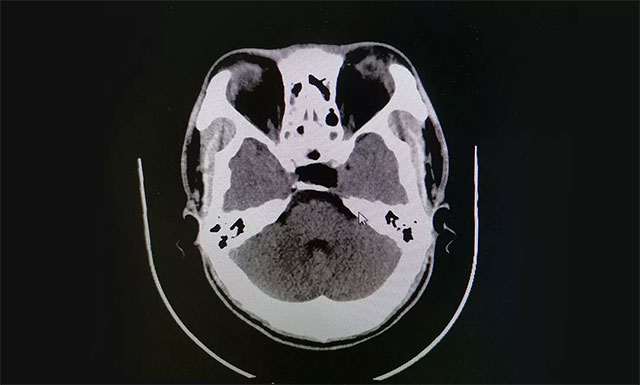

入院时,患者已经连续9天阵发性头痛,经检查其左侧眼睑有轻微下垂,约1米距离时有视物重影等症状,双眼视力0.2,四肢指关节较之前变粗大。针对患者情况,6B病区主任潘仁龙基于多年临床经验立即作出判断,急行头颅鞍区MRI平扫+增强,显示:蝶鞍显著扩大,鞍底下陷,鞍区见一不规则肿块,大小约1.6*3.2*2.1cm,病变向周围生长,突入鞍上池,推移视交叉,向下生长,鞍底受压,向鞍旁生长,海绵窦推挤改变。

▲ 术前影像:垂体大腺瘤,超蝶鞍生长,侵袭海绵窦

由潘仁龙主任、李士其教授、吴治群博士组成的专家组指出,根据患者影像学检查及检验结果分析,患者考虑为垂体大腺瘤伴卒中,患者面容有改变,怀疑为生长激素腺瘤。脑垂体瘤腺瘤出血,压迫了视网膜及海绵窦内的动眼神经,导致动眼神经麻痹,视物重影。